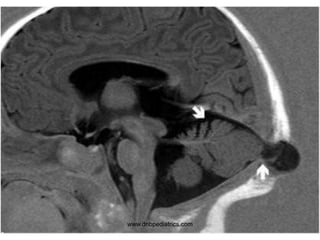

1. Infarct in the left basal ganglia, the

posterior limb of internal capsule, and the

head of the caudate

2. C Caudate

nucleus

T Thalamus

P Putamen

G Globus pallidus

White arrows indicate

the ant and post limbs

of internal capsule

3. Sickle cell anemia

4. Compression of 3rd cranial nerve